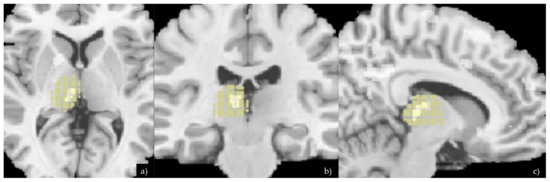

| Study > Control Group | x | y | z | Voxel Cluster | p-Values |

|---|---|---|---|---|---|

| Medio-dorsal Nucleus of the L-Thalamus | −10.5 | −21 | 6 | p < 0.001 | |

| Left Putamen Left Insula | −15 –42 | 18 15 | −6 1.5 | 694 29 | p < 0.001 p < 0.04 |